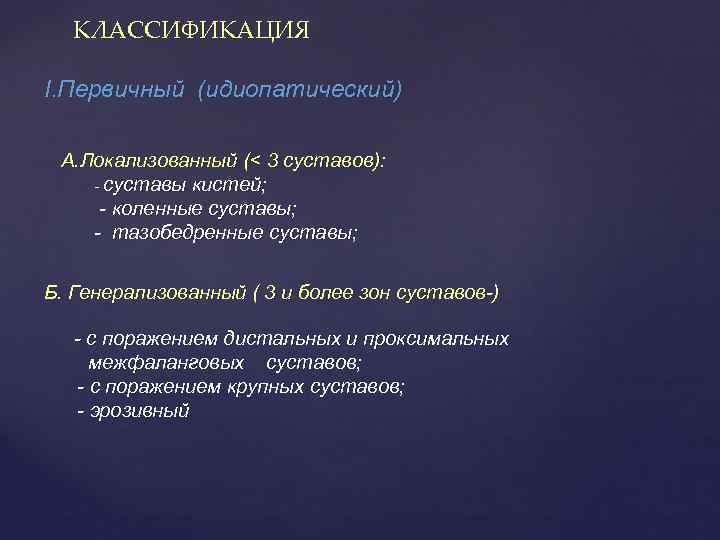

КЛАССИФИКАЦИЯ I. Первичный (идиопатический) А. Локализованный (< 3 суставов): - суставы кистей; - коленные суставы; - тазобедренные суставы; Б. Генерализованный ( 3 и более зон суставов-) - с поражением дистальных и проксимальных межфаланговых суставов; - с поражением крупных суставов; - эрозивный

КЛАССИФИКАЦИЯ I. Первичный (идиопатический) А. Локализованный (< 3 суставов): - суставы кистей; - коленные суставы; - тазобедренные суставы; Б. Генерализованный ( 3 и более зон суставов-) - с поражением дистальных и проксимальных межфаланговых суставов; - с поражением крупных суставов; - эрозивный

II. Вторичный А. Посттравматический Б. Врожденные, приобретенные или эндемические заболевания (болезнь Пертеса, синдром гипермобильности и др. ) В. Метаболические болезни (охроноз, гемохроматоз, болезнь Вильсона и др. ). Г. Эндокринопатии (акромегалия, гиперпаратиреоз, сахарный диабет, ожирение ) Д. Болезнь отложения кальция (фосфат кальция, гидроксиапатит) Е. Нейропатии (болезнь Шарко) Ж. Другие заболевания (аваскулярный некроз, РА, болезнь Педжета) По МКБ-X исключены: артроз межпозвонковых суставов; артроз 1 -го плюсне-фалангового сустава стопы

II. Вторичный А. Посттравматический Б. Врожденные, приобретенные или эндемические заболевания (болезнь Пертеса, синдром гипермобильности и др. ) В. Метаболические болезни (охроноз, гемохроматоз, болезнь Вильсона и др. ). Г. Эндокринопатии (акромегалия, гиперпаратиреоз, сахарный диабет, ожирение ) Д. Болезнь отложения кальция (фосфат кальция, гидроксиапатит) Е. Нейропатии (болезнь Шарко) Ж. Другие заболевания (аваскулярный некроз, РА, болезнь Педжета) По МКБ-X исключены: артроз межпозвонковых суставов; артроз 1 -го плюсне-фалангового сустава стопы